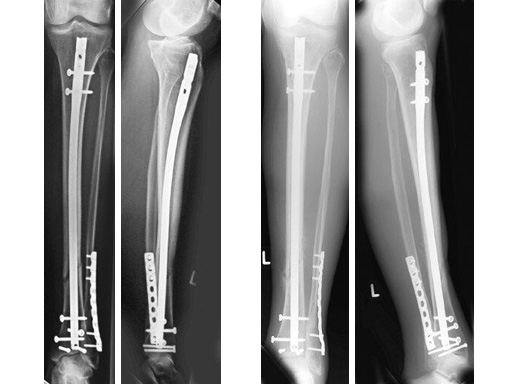

47-year-old man with closed 42-C3 fracture following a sports accident treated with ETNS.

60-year-old man with a type II open 42-A2 fracture following a working accident.